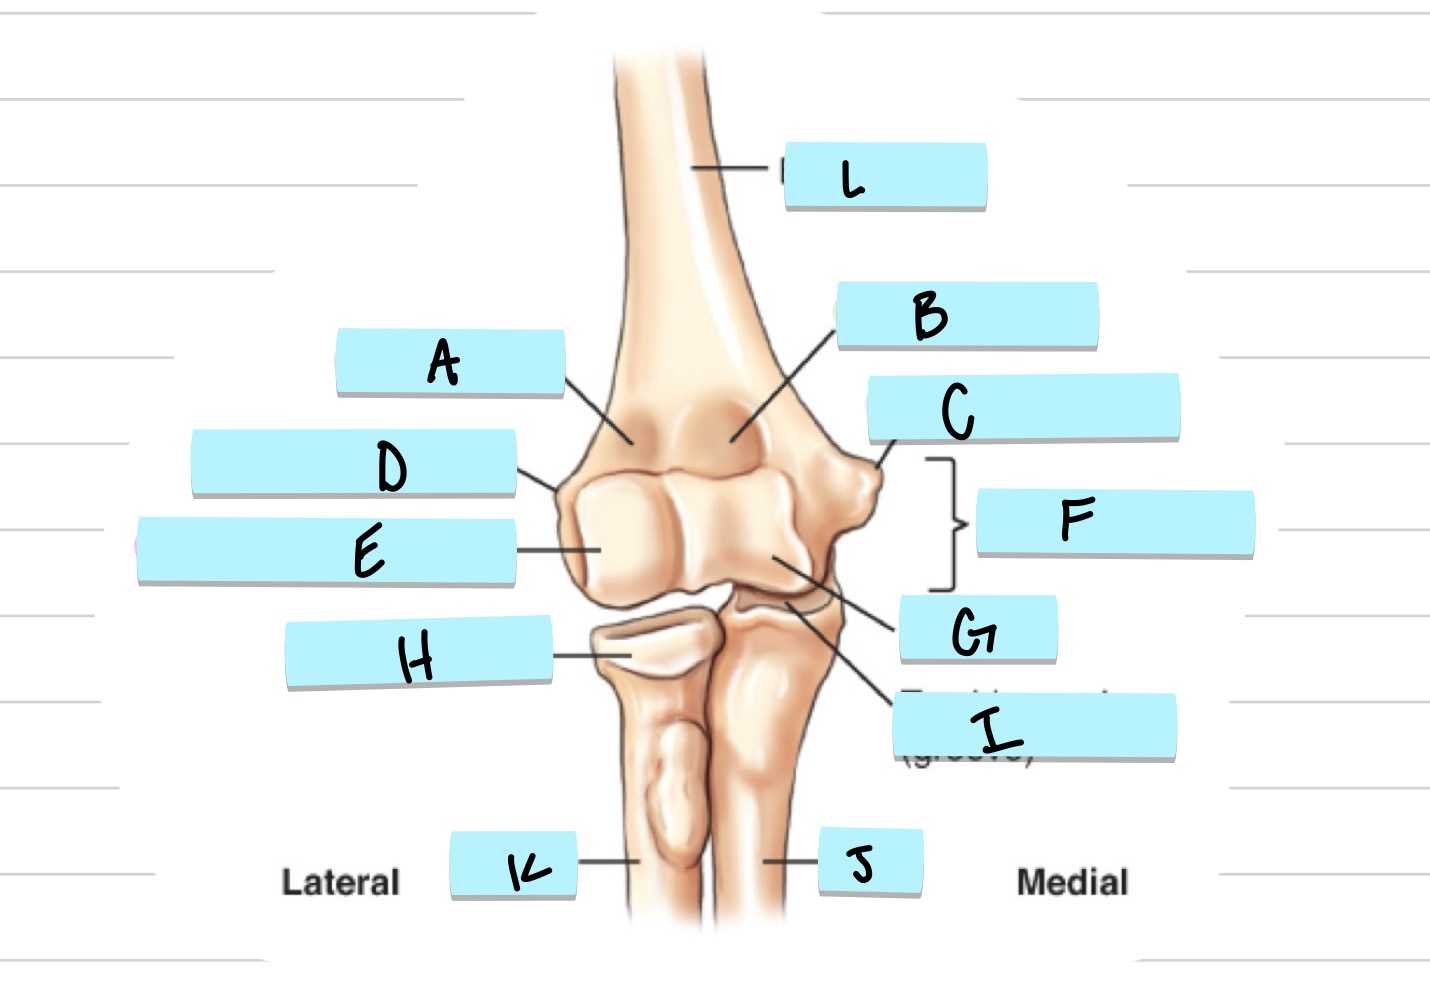

<p>What is A?</p>

What is A?

olecranon process

New cards

<p>what is B?</p>

what is B?

trochlear notch

37

<p>what is C?</p>

what is C?

coronoid process

38

<p>what is D?</p>

what is D?

radial notch